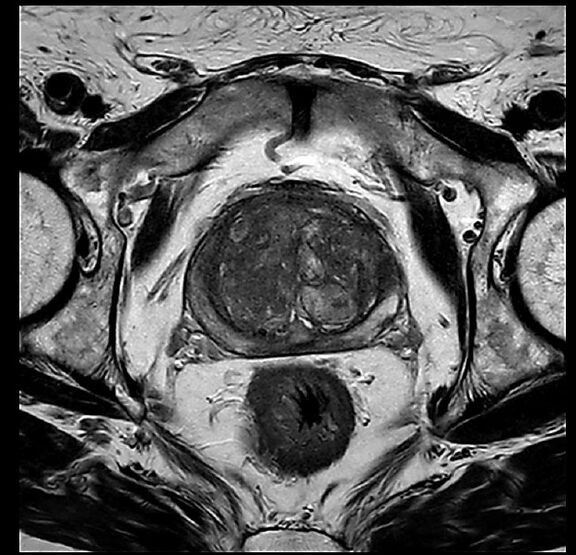

Beispiele von MRT-Prostata Aufnahmen

Die multiparametrische MRT (mpMRT) ist eine spezielle Form der MRT-Untersuchung, die zur Diagnose von Prostatakrebs eingesetzt wird. Im Vergleich zur herkömmlichen MRT bietet die mpMRT eine höhere Treffsicherheit bei der Erkennung von Prostatakrebs, da sie mehrere Parameter miteinander kombiniert. Dazu gehören unter anderem die Signalintensität des Prostatagewebes, die Durchblutung und die Diffusion von Wassermolekülen im Gewebe.

Die MRT wird meist zur Abklärung von Auffälligkeiten in der Prostata eingesetzt, die bei anderen Untersuchungen wie einer Tastuntersuchung, einer Blutuntersuchung oder einem PSA-Test festgestellt wurden. Dazu gehören zum Beispiel eine Vergrößerung der Prostata oder der Verdacht auf Prostatakrebs. Neben der Diagnose von Prostatakrebs können auch andere Erkrankungen wie Entzündungen oder gutartige Vergrößerungen der Prostata im MRT erkannt werden. Dies ermöglicht eine gezielte und schnelle Therapie.

Ein großer Vorteil der MRT im Vergleich zu anderen Verfahren ist die hohe Genauigkeit bei der Erkennung von Prostatakrebs im Vergleich zu anderen Verfahren. Die MRT kann die Gewebestrukturen der Prostata gezielt abbilden und so kleinste Veränderungen sichtbar machen. Zudem ist die Untersuchung schonender und kommt ohne den Einsatz von Röntgenstrahlung aus.